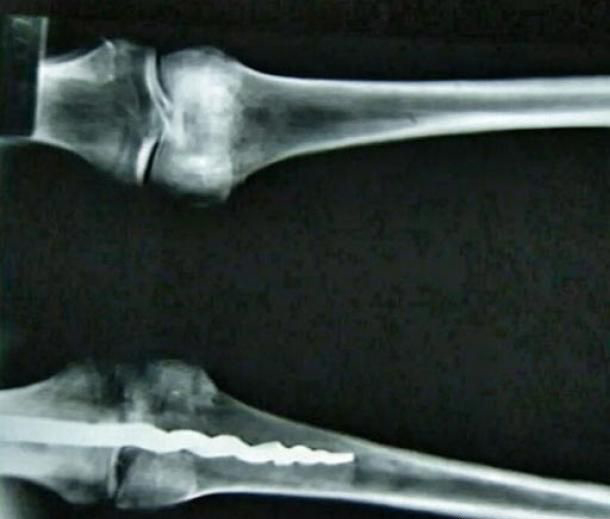

研究期间,他们有了惊人的发现:在Usermontu 的左膝中发现了一根9英寸(23公分)的金属螺丝钉,它连接着大腿和小腿,证明将近2600年前就曾实施先进的外科手术。

科学团队发现古代有机树脂的痕迹,它固定了钉子,可媲美现代的骨水泥(bone cement),他们还发现了古代脂肪和织品的残留物。

考古学家认为,在插入这根钉子前,这位祭司可能已死亡。先前展出的所有埃及木乃伊都没有这种特征。